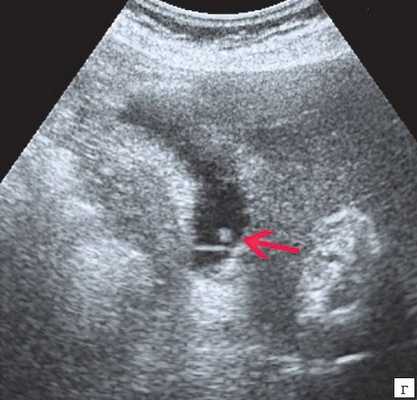

Из 53 детей с травмой живота ультразвуковое исследование проводилось у 36: у двух выявлен разрыв печени, у одного — разрыв селезенки, у одного — разрыв печени и селезенки.

На УЗИ это проявлялось наличием повреждения целостности органа и свободной жидкостью в брюшной полости, у остальных — было вздутие петель кишечника.

Рис. 1. Подкапсульная гематома печени

Рентгенологически при разрывах полого органа — свободный газ, при разрывах паренхиматозных органов — свободная жидкость в нижних отделах брюшной полости, при тупой травме — вздутие петель кишечника, нечеткость контуров их и, иногда, неравномерное распределение, как петель, так и его содержимого.